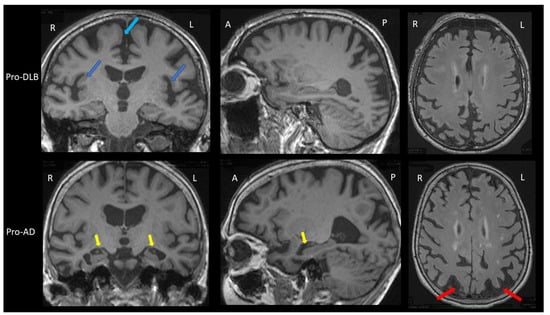

| Brain MRI T1 | Insular atrophy | Not demonstrated | No or mild hippocampal atrophy | Sensitivity = 64% Specificity = 68% (compared to AD) | [30] |

| Brain MRI SWI | Loss of the swallow tail sign | Not demonstrated | Loss of the swallow tail sign | Sensitivity = 63% Specificity = 75% (compared to AD) | [32] |